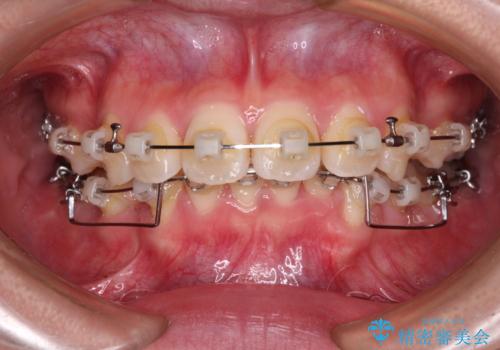

- クリアブラケット

- 3年9ヶ月

深い咬み合わせの改善に時間がかかりましたが、下顎前歯がしっかりと見えるまでに整えることができ、口元の突出感も大幅に改善することができました。